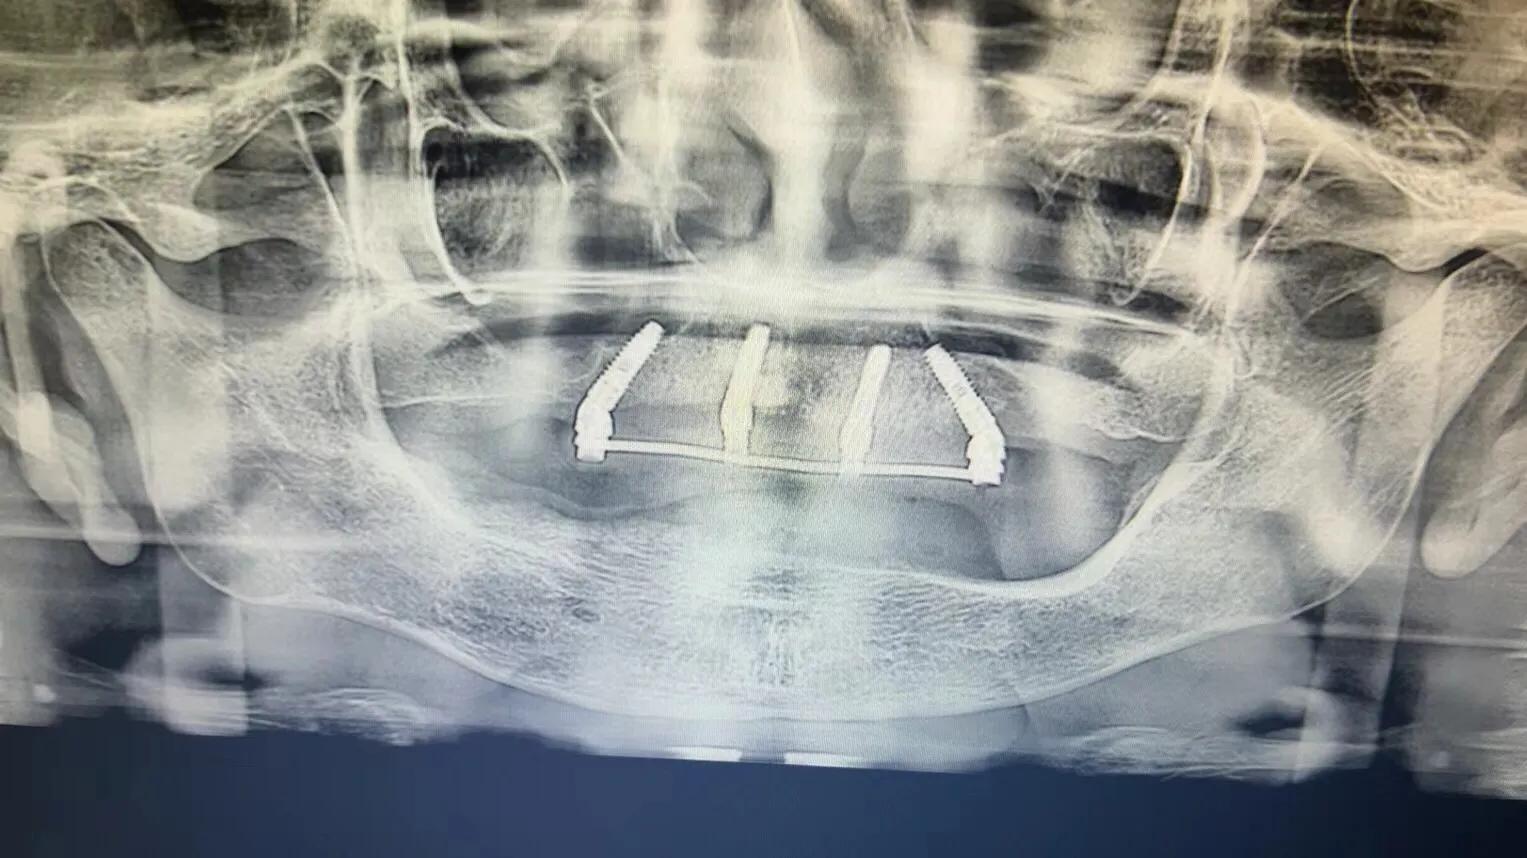

典型的負(fù)重,All-On-4。

這就是傳說中的當(dāng)天戴牙當(dāng)天吃飯,網(wǎng)上到處宣傳的就是這種種植方法。但是不是每一個(gè)人都能做這個(gè),All-on-4一般需要預(yù)約,醫(yī)生種植完畢,技師馬上開始取模做牙,大概5小時(shí)左右就可以戴上臨時(shí)牙回家吃飯了,休息一兩天,正常吃飯是沒問題的。

2. 還有一個(gè)問題就是骨件,不是每個(gè)人都可以做。骨頭太差,只能做常規(guī)的種植,等3-6個(gè)月戴牙,可能更久,中間只能用臨時(shí)牙過度。負(fù)重開始戴的也是臨時(shí)牙,但是這個(gè)臨時(shí)牙和常規(guī)島臨時(shí)牙不一樣,咬合力挺好

3. 有些患者以為一顆牙也可以這樣,一顆是不行的,至少連續(xù)4顆才可以,比如門牙連續(xù)4顆就可以做。